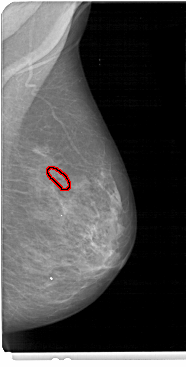

A_1465_1.RIGHT_CC

FILE: A_1465_1.RIGHT_CC.OVERLAY

TOTAL_ABNORMALITIES 1

ABNORMALITY 1

LESION_TYPE CALCIFICATION TYPE FINE_LINEAR_BRANCHING DISTRIBUTION LINEAR

ASSESSMENT 5

SUBTLETY 3

PATHOLOGY MALIGNANT

TOTAL_OUTLINES 1

BOUNDARY